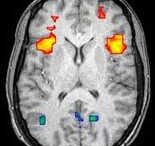

Η συναναστροφή μας με άτομα άλλης εθνικότητας μπορούν να ενεργοποιήσουν…